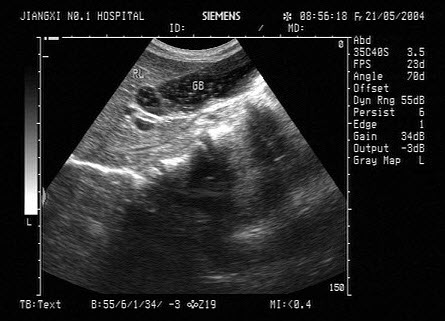

2、单项选择题

女,42岁,反复上腹疼痛不适多年,加重3天。声像图如图所示,最可能的诊断为()

A.胆囊泥沙样结石

B.胆囊蛔虫

C.胆囊癌

D.胆囊息肉

E.胆汁淤积